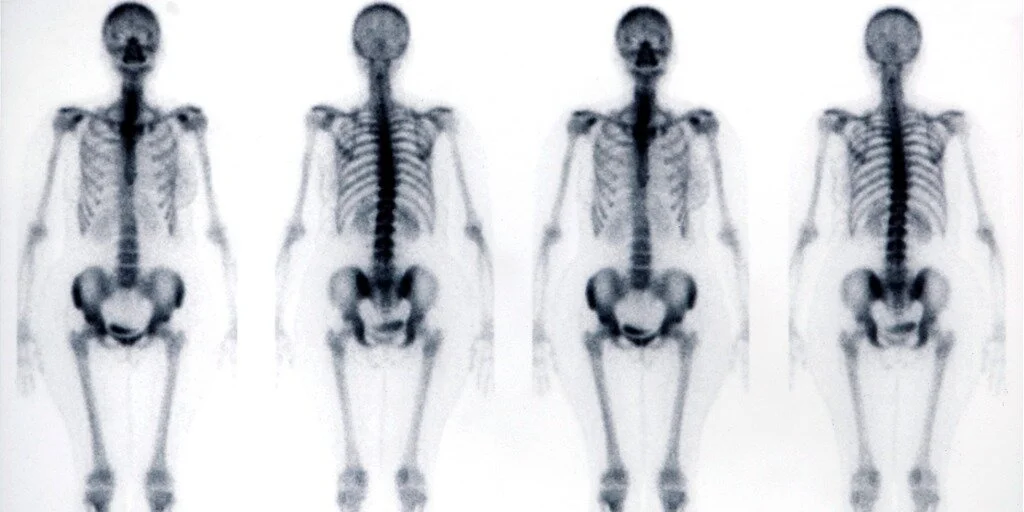

46+ Nuclear Bone Scan Images UK. It's also known as skeletal scintigraphy. The nuclear bone scan procedure is not invasive and is, for the most part, painless.

The nuclear bone scan procedure is not invasive and is, for the most part, painless. Bone scans are very sensitive, but not specific. Nuclear bone scan stock photos and images.

A bone scan images the metabolic activity of the skeleton.

A bone scan uses radionuclides to create images of bones where there is cancer, infection or damage. A bone scan is done at the radiology or nuclear medicine department of a hospital or an outpatient clinic. Your doctor may recommend a bone scan if they suspect you have osteoporosis (brittle bones), a fracture, bone. A bone scan is a nuclear medicine test.